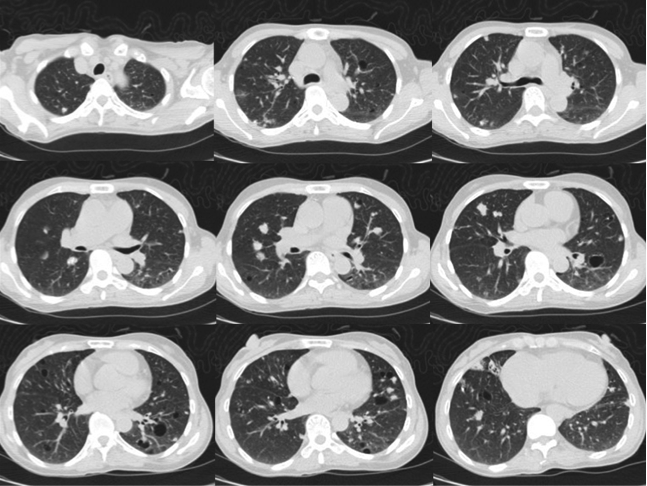

The patient was a chronic smoker (30 pack-years) and chronic drinker. He was a construction site worker and his past health was good. He presented with headache for a few weeks and was found to have signs of superior vena cava obstruction (SVCO). He did not have other complaint and the rest of the physical examination was normal. His CXR was unremarkable (Fig 4). His plain CT brain was also unremarkable. His initial blood tests including complete blood picture, renal & liver function test, erythrocyte sedimentation rate, urate, lactate dehydrogenase and tumor markers (including carcinoembryonic antigen, alpha-fetoprotein and prostate-specific antigen) were normal. His sputum was negative for culture, acid fast bacilli and cytology. His contrast CT thorax showed enlarged lymph nodes (LN) in the right lower paratracheal, pre-carinal & right hilar region and aorto-pulmonary window. The enlarged right lower paratracheal and precarinal LN compressed the brachiocephalic veins and superior vena cava (Fig 5). FOB with transbronchial needle aspiration under endobronchial ultrasound guidance (EBUS-TBNA) were done. The specimen of the right lower paratracheal LN was reported as suboptimal while the specimen from the right hilar LN was negative for any significant pathology. In view of SVCO was a potential medical emergency, we suggested surgical biopsy of the mediastinal LNs to ascertain their nature more definitively in order to guide subsequent management. He was then referred to the thoracic surgery clinic and PET-CT was done as suggested by the thoracic surgeon. The PET-CT was reported as “There were multiple enlarged hyper-metabolic mediastinal LNs (SUVmax 3.3-6.5) and the provisional diagnosis would include lymphoproliferative disease.” A hypermetabolic focus (1.7cm x 1.0cm x 2.3cm, SUVmax = 4.7) in the periphery of the right vastus lateralis muscle was also found incidentally (Fig 6A, 6B). At that juncture, the working diagnosis was SVCO due to possible lung carcinoma with LN metastases or lymphoma. The right thigh lesion could be part of the disease or something unrelated. Right anterior mediastinotomy and biopsy of the right lower paratracheal LN were done. Histology showed a piece of fibrous tissue with marked suppurative granulomatous inflammation. However, infective stains including Ziehl-Neelsen (ZN) stain were negative. His tuberculin skin test was 24mm (that was strongly positive) and his histoplasma antibody was negative. Standard anti-tuberculosis (TB) treatment was started and the signs of SVCO resolved progressively. Later, ultrasound guided FNA of his right thigh lesion showed granulomatous inflammation and one acid fast bacillus. Thus the final diagnosis was TB mediastinal lymphadenopathies causing SVCO, and right thigh TB infection. An interval CT about four months after anti-TB treatment showed the mediastinal LNs were decreased in size.

Figure 5